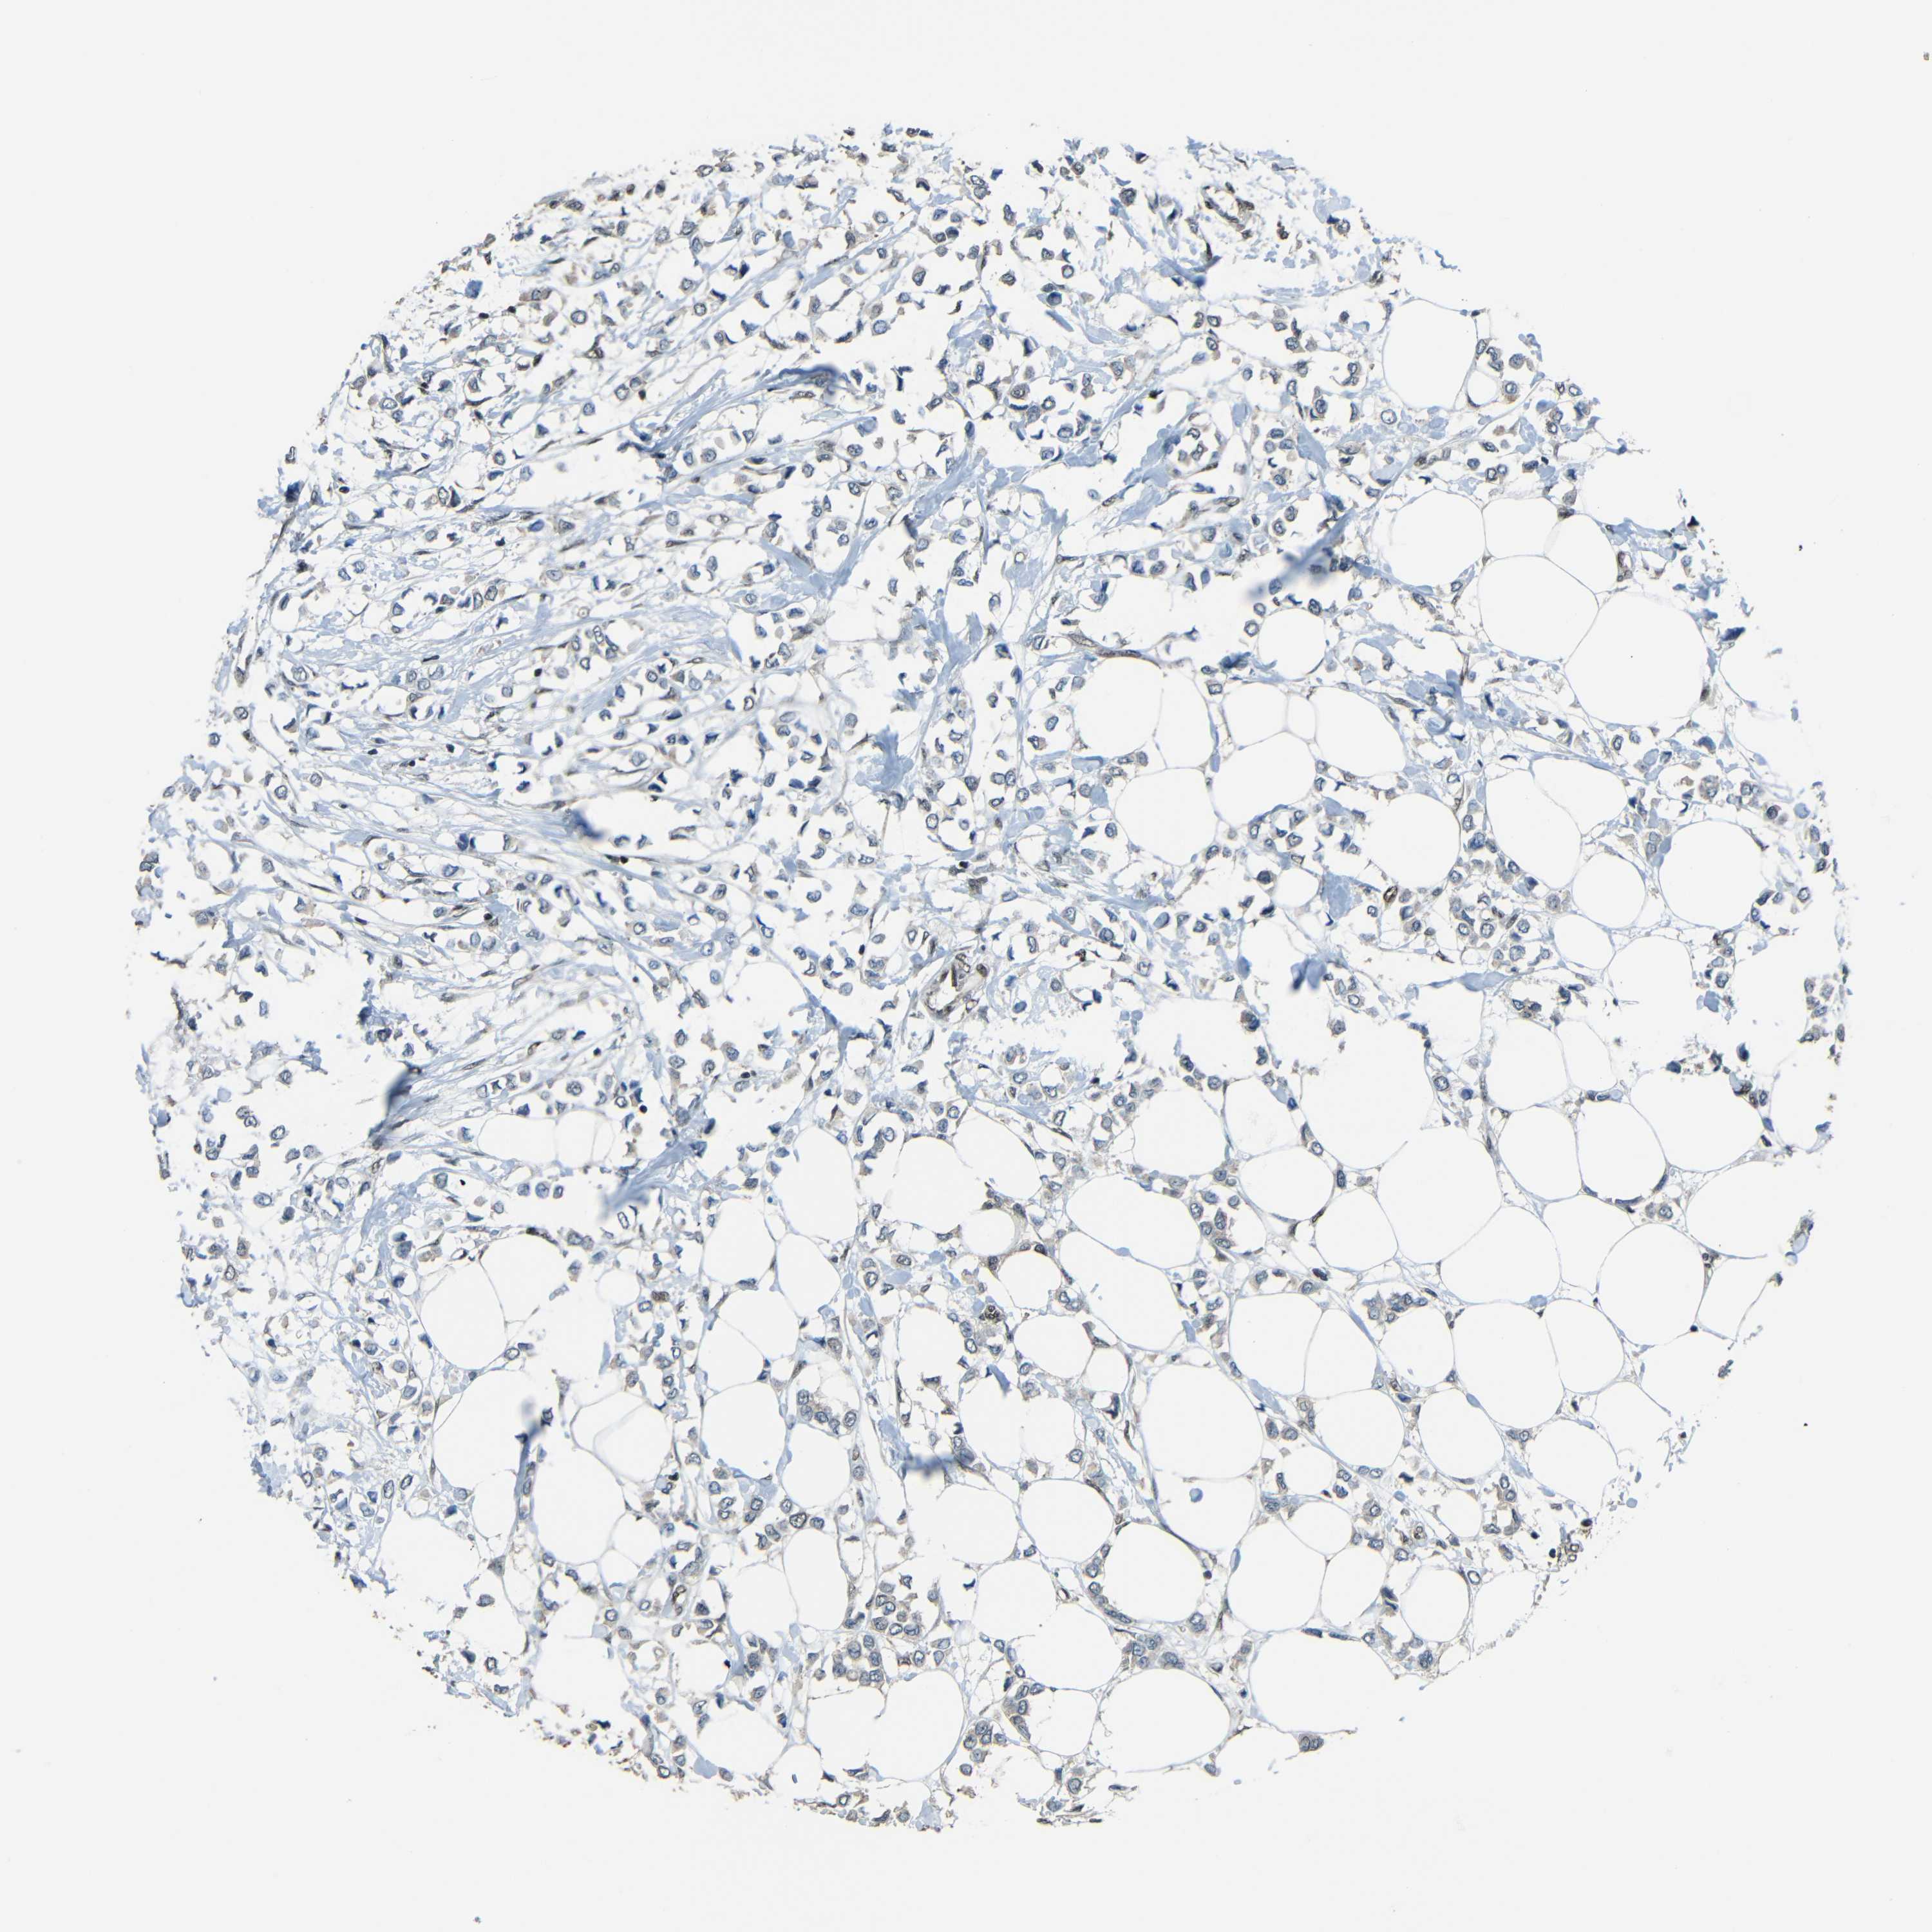

CANCER BREAST CANCER Show tissue menu

BRCA TCGA BRCA VALIDATION PROTEIN EXPRESSION